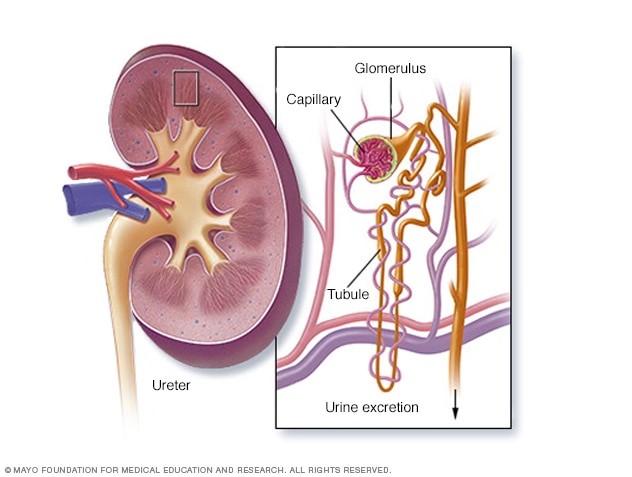

Thận là một cặp cơ quan nằm ở phần dưới xương sườn về phía lưng của bạn. Mỗi bên cột sống sẽ có một quả thận tương ứng. Chúng có chức năng lọc máu và loại bỏ độc tố khỏi cơ thể. Thận thải chất độc theo nước tiểu đến bàng quang, sau đó loại bỏ chất độc ra khỏi cơ thể qua quá trình đi tiểu.

Suy thận xảy ra khi thận của bạn mất chức năng lọc máu và thải độc, có thể đe dọa tính mạng nếu không được điều trị. Nhiều yếu tố có thể ảnh hưởng đến chức năng thận của bạn là: